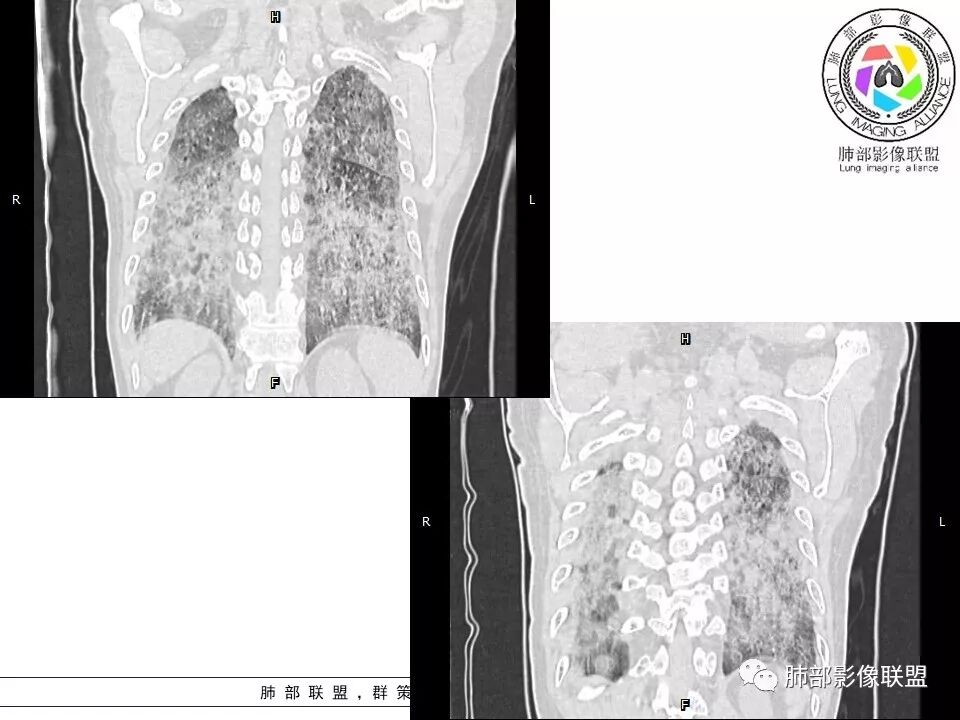

碎石路征,下肺为主

肺血坠积

南边:只有GGO+网格(小叶间隔增厚),然后就是分布的问题

1、GGO+网格——碎石路征

2、分布无特定位置,较随机

5、病灶较多时部分可见重力趋势

1.由于脂蛋白的沉积和占据,肺泡腔含气量减少,这是影像上较大范围“磨玻璃影”的基础。

2.由液体、细胞浸润和纤维组织造成的小叶间隔增厚是影像上多边形“铺路石征”的基础。

3.显眼的小叶间隔对病灶有阻挡作用是形成影像上“地图样改变”的基础。我们观察到的病灶与临近相对正常肺组织之间常常有比较清楚的分界。

4.病灶常多发,但心尖区及膈角区相对轻微。